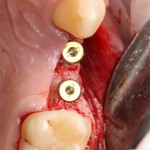

Например, в следующей ситуации:

Оставить так, как есть — это значит, сильно рисковать имплантом и объемом альвеолярного гребня — фактически, большая часть импланта пятого зуба «висит в воздухе». Поэтому получившуюся костную полость мы заполняем аутокостной стружкой в смеси с Bioss и закрываем коллагеновой мембраной BioGide: